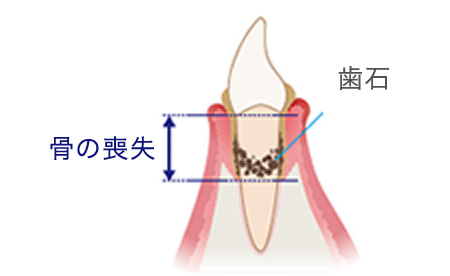

歯茎の溝(歯周ポケット)に隠れたプラーク(細菌の塊)によって発症します。歯垢は歯ブラシやうがいである程度落とすことはできますが、全て取り除くことは不可能と言われていおり、磨き残された歯垢はやがて歯石となってしまいます。歯石には小さな穴や隙間があり、そこが新たな細菌の住処となります。こうして細菌はどんどんお口の中で繁殖し、歯周病は悪化していきます。

中度歯周炎

歯周ポケットが形成され、歯石が深部まで付着し、歯を支える骨を半分くらい失っています。